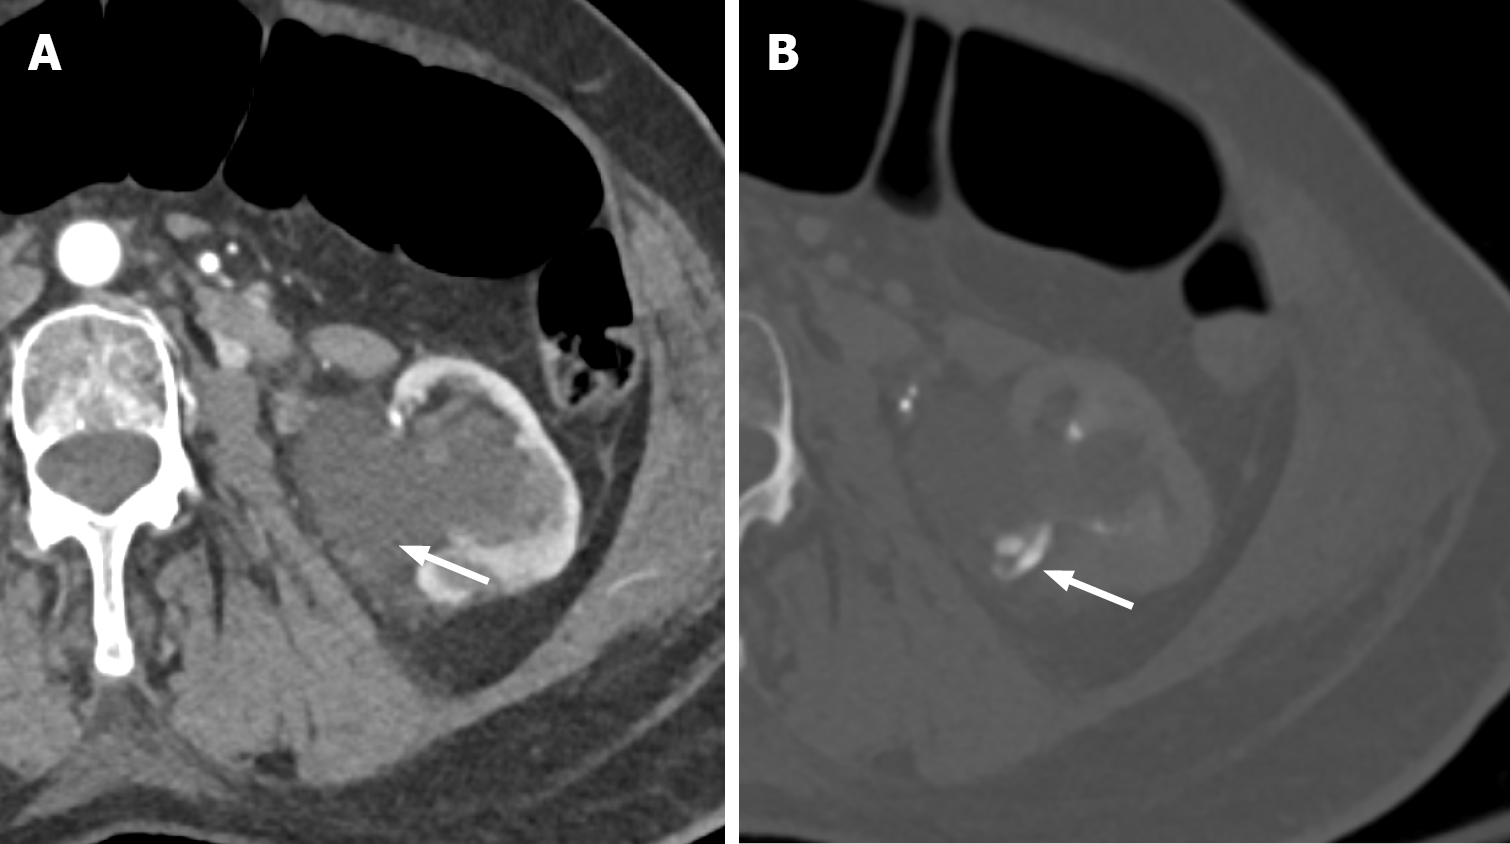

Figure 7 Renal artery dissection.

A: Coronal view computed tomography of the abdomen in arterial phase demonstrates linear hypoattenuation within the right mid renal artery, suggesting dissection (white arrow). Note the infarcted kidney (black arrow); B: Axial view confirming the dissection flap within the right renal artery (white arrow); C: Right renal angiogram demonstrating the dissection flap within the right renal artery (white arrow); D: Successful stenting of the right renal artery (white arrow).